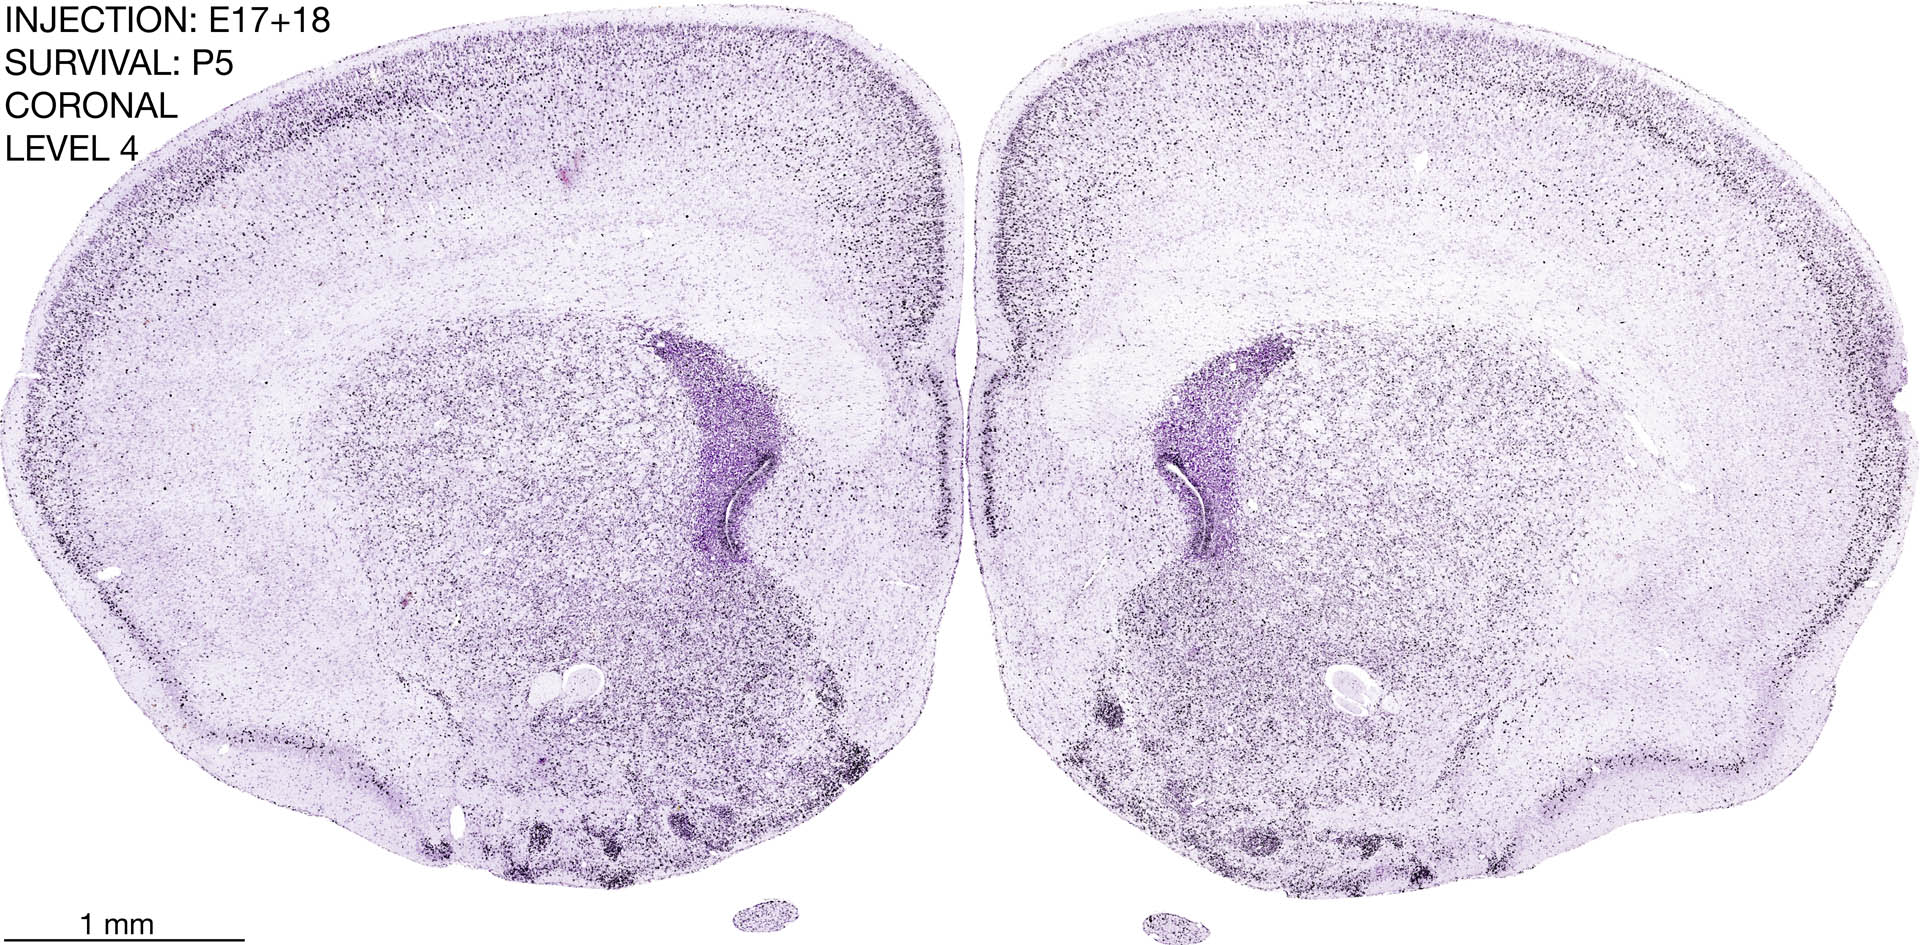

E17+18 P5 Survival The images below are from the brain of a rat that was exposed to tritiated thymidine on E17+18 and survived to P5. Download: Large | High Res Download: Large | High Res Download: Large | High Res Download: Large | High Res Download: Large | High Res Download: Large | High Res Download: Large | High Res Download: Large | High Res Download: Large | High Res Download: Large | High Res Download: Large | High Res Download: Large | High Res Download: Large | High Res Download: Large | High Res Download: Large | High Res Download: Large | High Res Download: Large | High Res Download: Large | High Res Download: Large | High Res Download: Large | High Res Download: Large | High Res Download: Large | High Res Download: Large | High Res Download: Large | High Res Download: Large | High Res Download: Large | High Res